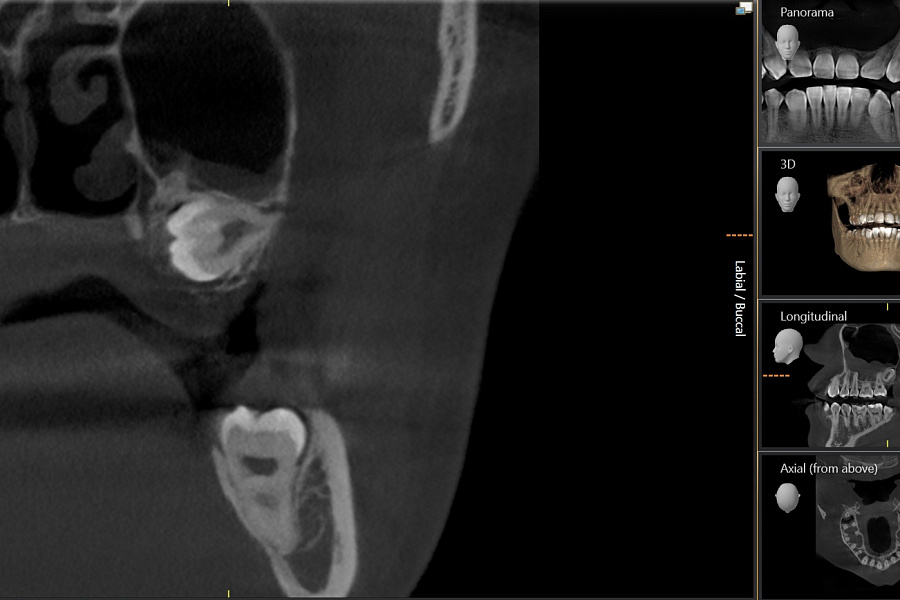

Зуб не прорезался, лежит горизонтально и направлен в сторону твёрдого нёба, мешает проведению ортодонтического лечения, выпрямлению зубных рядов. Около зуба проходит несколько важных анатомических структур, которые нельзя задеть, плюс зуб полностью погружён в костную ткань.